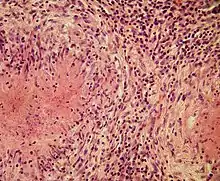

Structurally, epithelioid cells (when examined by light microscopy after stained with hematoxylin and eosin), are elongated, with finely granular, pale eosinophilic (pink) cytoplasm, and central, ovoid nuclei (oval or elongate), which are less dense than that of a lymphocyte.[4] They have indistinct shape and often appear to merge into one another, forming aggregates known as giant cells. When examined by transmission electron microscopy in epithelioid cells in the field of Golgi lamellar complex are taped not only zonated, but also sleek vesicles with dense center, and also great many (more than 100) large granulas with diameters up to 340 nm and with finegranular matrix more light than in macrophage granulas, sometimes with perigranular halo. “The most prominent feature of these cells is the enormous Golgi area; up to 6 individual stacks of Golgi cisternae may be present as well as a few bristle-coated and numerous smooth vesicles”.[5][4] Epithelioid cells have tightly interdigitated cell membranes in zipper-like arrays that link adjacent cells.[3] This cells are central in the formation of granulomas, which are associated with many serious diseases.[4] In granulomas, epithelioid cells perform the functions of delimiting.[3]

Fragment of the outer edge zone of tuberculosis epithelioid cell granuloma. In the lower part – a layer of epithelioid cells, in which Langhans giant cell begins to form, as a result of the fusion of epithelioid cells. In it, we can notice the division of the cell nucleus of epithelioid cells, from which smaller nucleus are formed. Single pycnotic and apoptotically altered macrophages are found among epithelioid cells. Above the zone of epithelioid cells is a layer of fibroblasts that form a kind of “capsule”. In the upper part – a layer of cells consisting of lymphocytes. The video shows the result of optical scanning (when using Phase-contrast microscopy) when changing the depth of field.

Epithelioid cells are an essential characteristic of epithelioid cell granulomas.[10] Epithelioid cell granuloma can be defined as specifically and structurally organized collection of epithelioid cells, macrophages, lymphocytes and dendritic cells. Foreign-body granulomas may be considered an organized collection of macrophages, including mere collections of giant cells surrounding inert substances like suture material – the so-called "non-immune granulomas." Granuloma formation is associated with pathogens that have learned to evade the host immune system by various means like resisting phagocytosis and killing within the macrophages. Indigestibility of matter by macrophages is a common feature of granulomatous inflammation.[4] Granulomas try to wall off these organisms and prevent their further growth and spread. Historically widespread and destructive diseases such as tuberculosis, leprosy and syphilis are granulomatous conditions. Granuloma formation is also the feature of many more contemporary conditions, like fungal infections, sarcoidosis and Crohn's disease.[4]